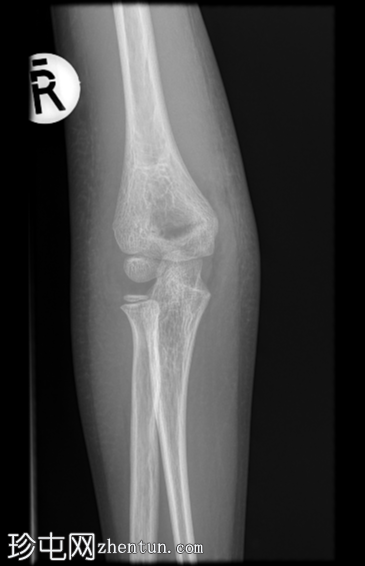

X线片

正位片

右侧肱骨远端Gartland I型髁上骨折。无急性脱位。肘关节前后脂肪垫突出,提示肘关节积液。桡骨近端和尺骨近端正常。